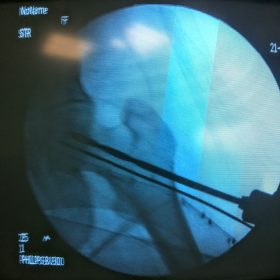

Διατροχαντήριο : Εξωαρθρικό κάταγμα, στην περιοχή ανάμεσα στο ελάσσονα και το μείζονα τροχαντήρα. Αντιμετωπίζεται χειρουργικά με ενδομυελική ήλωση τύπου γ-Nail. Δύο τομές 3 εκατοστών και 1 εκατοστού αντιστοίχως για την εισαγωγή και το κλείδωμα του ήλου μέσα στο οστό. Η μέθοδος είναι κλειστή,σχεδόν αναίμακτη,διάρκειας 30 λεπτών,με τη βοήθεια C-ARM (τηλεόρασης). Στον ασθενή παρέχεται οπτικό υλικό (όλα τα χειρουργικά στάδια) σε CD ή Στικάκι,λόγω της δυνατότητας καταγραφής του χειρουργείου από το C-ARM Ο ασθενής περπατάει άμεσα μετεγχειρητικά στις 5 ώρες μετά την επέμβαση και εξέρχεται από το νοσοκομείο σε 1 -2 ημέρες.

Υποτροχαντήριο :Εξωαρθρικό κάταγμα κάτω από τον ελάσσονα τροχαντήρα του μηριαίου οστού. Αντιμετωπίζεται χειρουργικά με ενδομυελική ήλωση τύπου Long γ-Nail. Δύο τομές 3 εκατοστών και 1 εκατοστού αντιστοίχως για την εισαγωγή και το κλείδωμα του ήλου μέσα στο οστό. Η μέθοδος είναι κλειστή,σχεδόν αναίμακτη,διάρκειας 60 λεπτών,με τη βοήθεια C-ARM (τηλεόρασης). Στον ασθενή παρέχεται οπτικό υλικό (όλα τα χειρουργικά στάδια) σε CD ή Στικάκι,λόγω της δυνατότητας καταγραφής του χειρουργείου από το C-ARM Ο ασθενής περπατάει άμεσα μετεγχειρητικά στις 5 ώρες μετά την επέμβαση και εξέρχεται από το νοσοκομείο σε 1 -2 ημέρες.